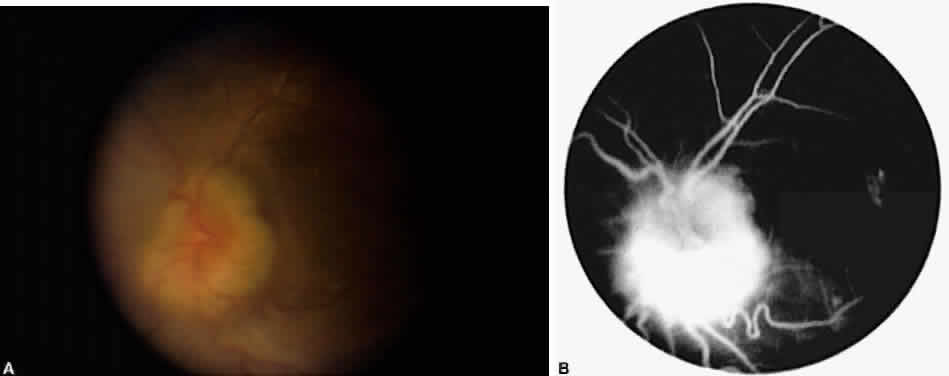

Cystoid macular edema (CME) is by far the most common macular sequela of chronic inflammation, although retinal and subretinal neovascularization, preretinal membranes, macular ischemia, and macular holes can also occur.41–43 Chronic CME and its sequelae are a significant cause of visual morbidity and probably account for the majority of cases of low visual acuity (20/40) in uveitis patients (Fig. 5).44–46 The main symptoms experienced by patients with CME are decreased vision and metamorphopsia, often with marked fluctuations in acuity. The diagnosis of CME is often difficult and may require careful stereoscopic examination at the slit lamp with a contact, Hruby, 78 or 90 D lens. Frank cystoid changes may not be present, and often only a loss of the normal foveal reflex is seen. For cases in which the diagnosis is not clear, fluorescein angiography is a helpful tool. This demonstrates leakage from perifoveal capillaries, with or without the characteristic petaloid hyperfluorescence in the late phases of the angiogram.

Fig. 5. Typical cystoid macular edema (CME) on fluorescein angiography in patient with chronic iridocyclitis. Note petaloid pattern of leakage around macula. Staining of the disc is often present.

When following uveitis patients with CME, it is important to realize that an improvement in visual acuity may occur before there is a decrease in capillary leakage on fluorescein angiography or a change in blood-retinal barrier permeability as measured with vitreous fluorophotometry.63,64,68 In fact, only retinal thickness has proved to correlate well with visual acuity.69 Thus, although fluorescein angiography is very helpful in making the diagnosis of CME, stereophotographs of the macula coupled with a good clinical examination may be a better way to follow a patient's response to treatment.